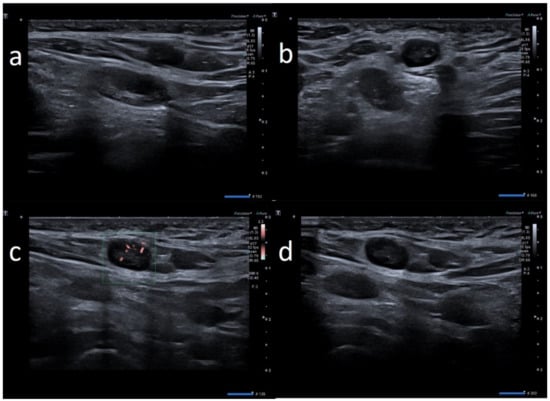

| W | 25 | Pfizer | Axillary ipsilateral to vaccine injection | Three days after first dose of vaccine, axillary swelling and pain present. Also hypomobility ipsilateral arm | None | 6 | Variable: from 0.7 cm to 2.8 cm | Ovular | Prev. no hilum evidence | Prevalent hard pattern | Central and peripheral vascular signals | Normalized to 60 days |

| W | 37 | Pfizer | Axillary ipsilateral to vaccine injection | Three days after first dose vaccine, axillary swelling present | Melanoma 5 years ago | 5 | Variable: from 1.5 to 2.0 cm. | Ovular | Assimetric cortical thickening with hilum evidence | Prevalent hard pattern | Central and peripheral vascular signals | Normalized to 45 days |

| W | 26 | Astazeneca | Supraclavicular ipsilateral to vaccine injection | 2 days after the first dose vaccine, axillary swelling and pain present | None | 5 | Subcentimetric size | Ovular | No hilum evidence | Prevalent hard pattern | Central and peripheral vascular signals | Normalized to 45 days |

| W | 28 | Astazeneca | Supraclavicular ipsilateral to vaccine injection | Two days after first dose vaccine, supraclavicular swelling and pain present | None | 3 | Variable: from 0.6 to 1.5 cm | Ovular | No evidence hilum | Prevalent hard pattern | Central and peripheral vascular signals | Normalized to 45 days |